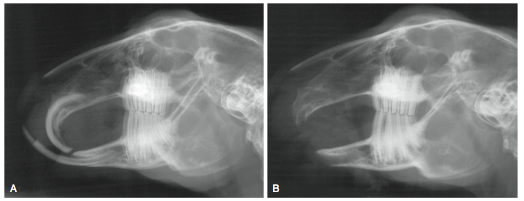

Small Mammal Dentistry

» Photos